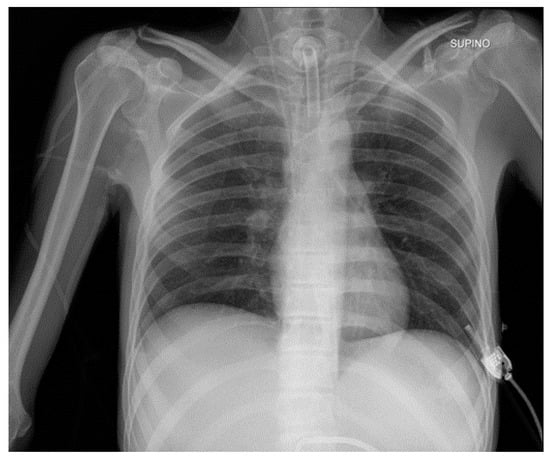

5.2. Pacemaker (PM) and Automatic Implantable Cardioverter-Defibrillator (AICD)

| PM and AICD | Leads misposition/breakage |

| Twiddler’s syndrome | |